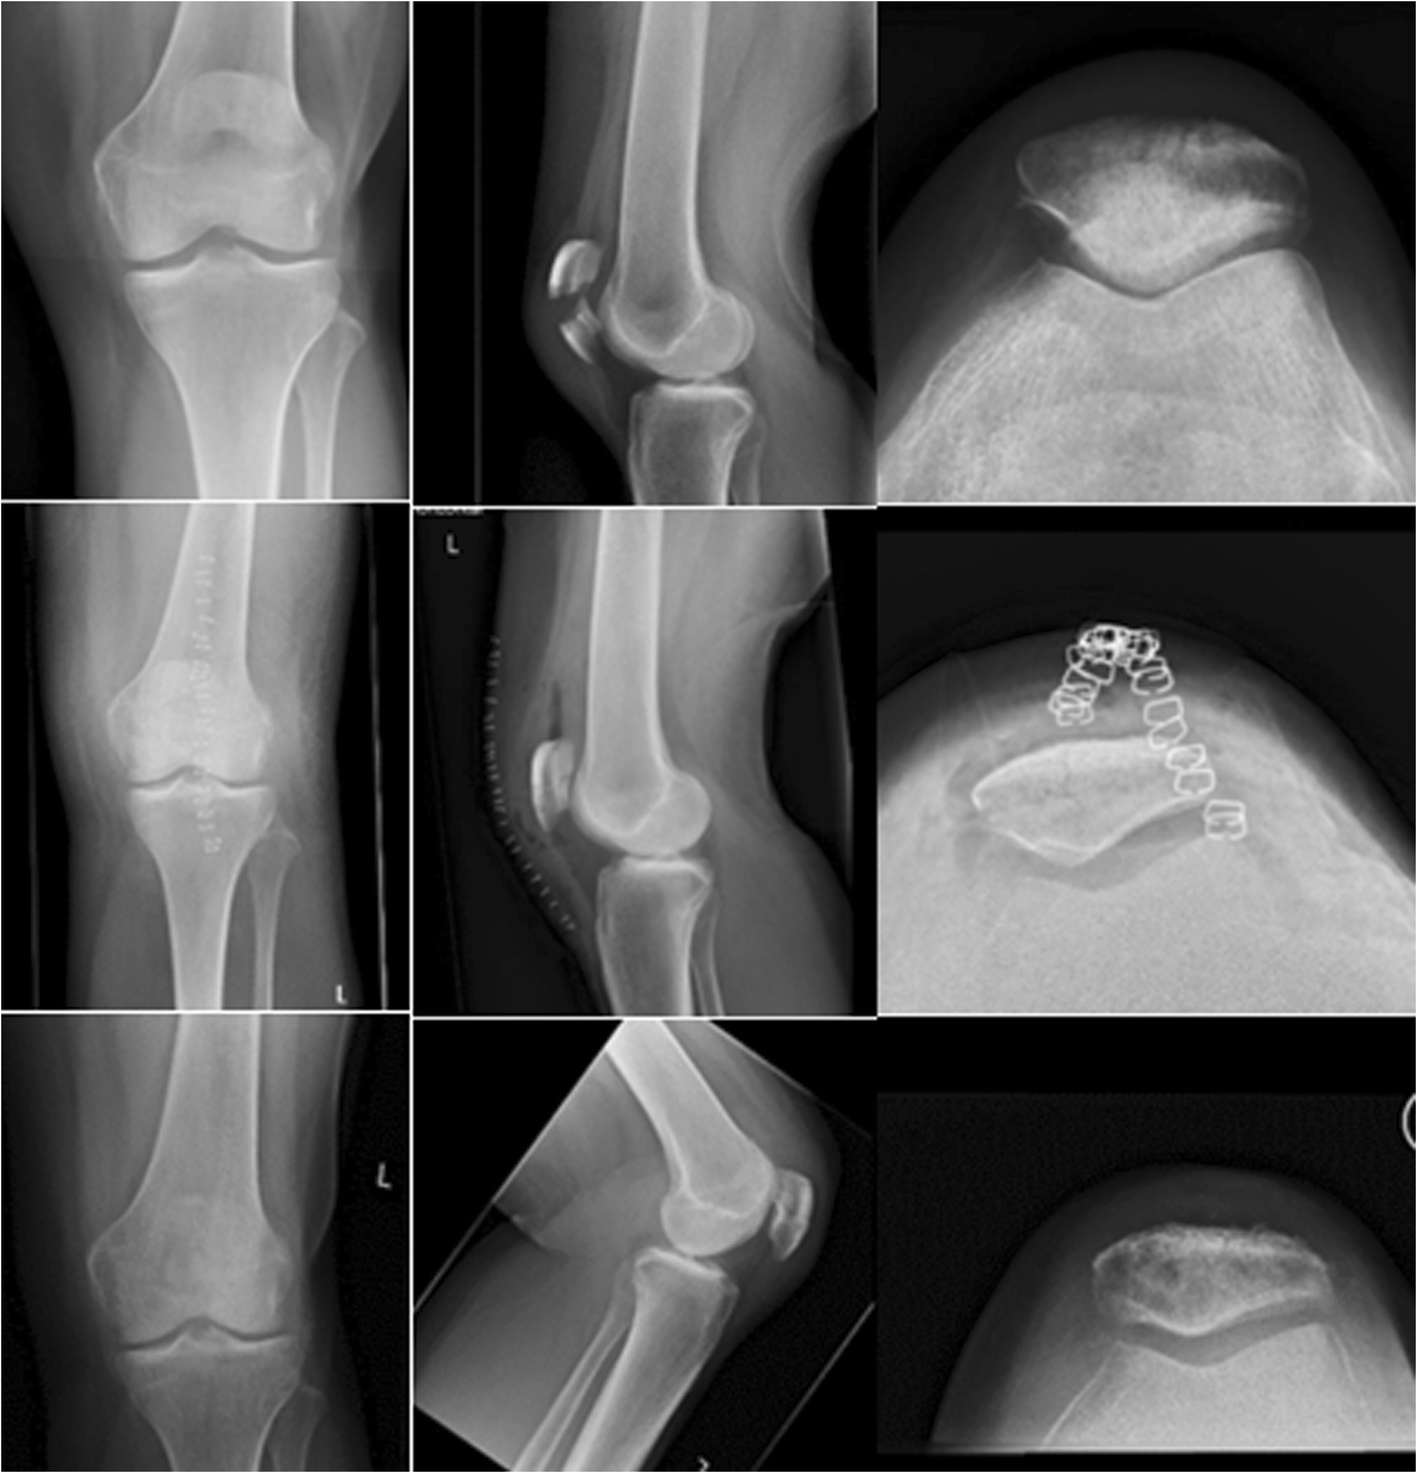

Pre-, post-, and 6-month postoperative X-rays (above, middle and below, respectively) of patient 6, a 58-year-old woman with a simple transverse patella fracture